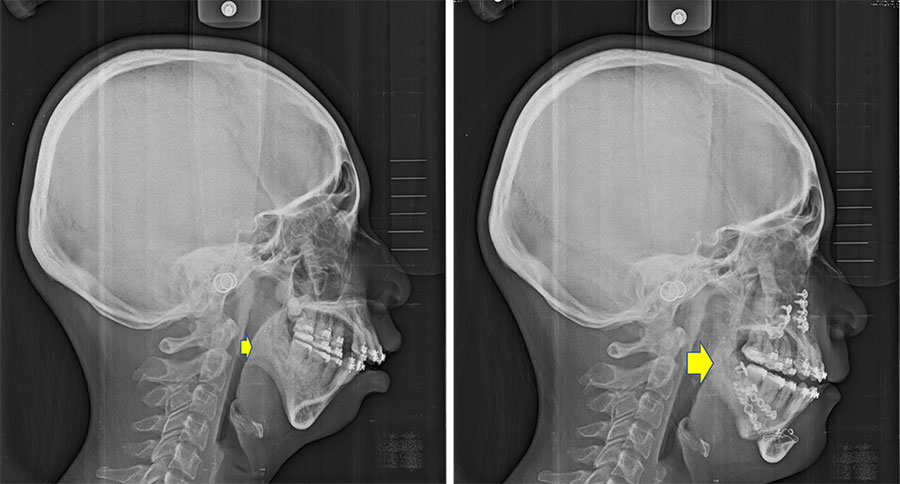

Illustratively, consider the case of Peter (Fig. 1a), afflicted with severe obstructive sleep apnea (AHI: 143; categorized as severe if above 30), possessing a short chin and a protruding upper jaw. Peter underwent tooth extraction and segmented osteotomy of the upper jaw, coupled with advancement and rotation of the lower jaw during surgery (Fig. 1b). This substantially augmented the volume of the oropharyngeal airway, alleviating airway obstruction (post-surgery AHI: 11). Additionally, the chin reshaping resulted in a more aesthetically pleasing facial appearance, bolstering Peter's self-assurance. Post-operative orthodontic treatment enhanced dental alignment, function, and esthetics (Fig. 1c).

A patient with small chin complaining of sleeping disturbance with snoring, and pre-op AHI: 8.5 was noted (Fig. 2a) underwent segmental Le Lefort I osteotomy with maxilla-mandibular advancement (Fig. 2b). Post-operative airway expansion has been achieved with reduction of AHI (AHI: 2.4) after orthognathic surgery. Three-dimensional airway change shows volume of pharyngeal airway has enlarged from 18965 mm3 to 22899 mm3 peri-operatively (Fig. 2c). The patient was happy with functional and esthetical improvement during the whole treatment. Similar study of airway change could be searched in the literature which addressed patients with cleft receiving orthognathic surgery5.